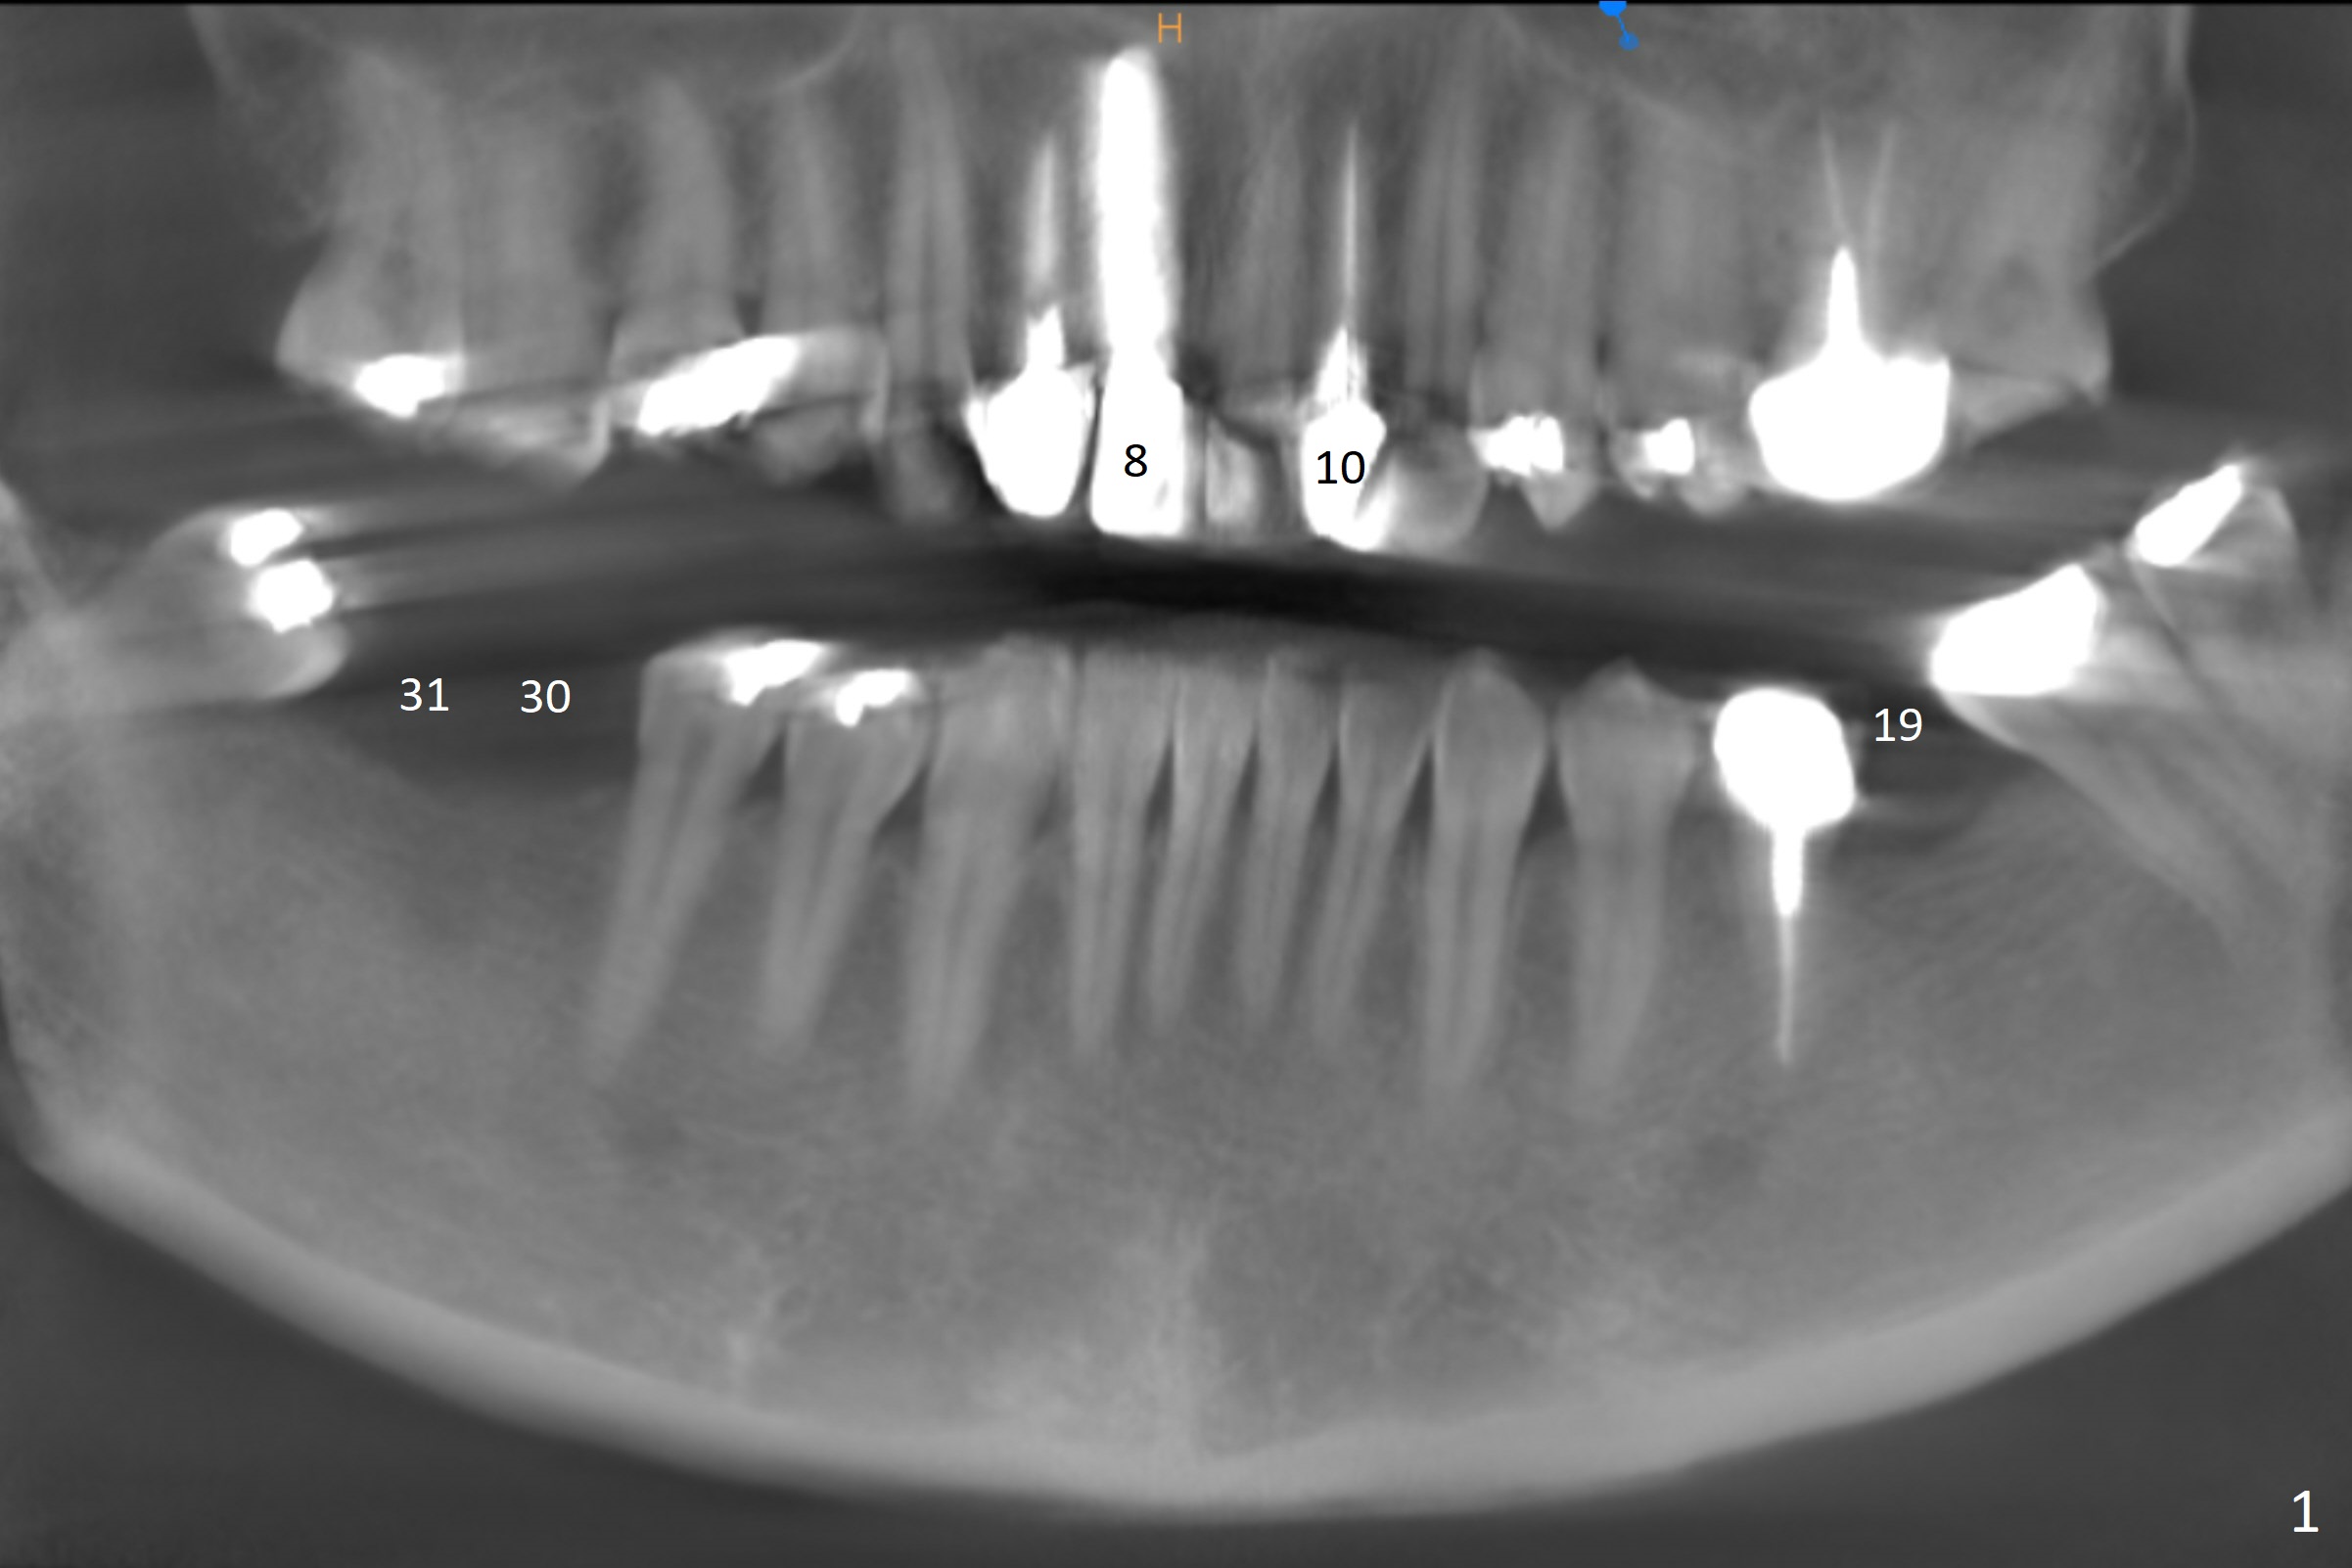

A healthy 37-year-old woman has 3 missing lower molars (Fig.1 panoramic view from CBCT). She has had implants at #8 and 10. The bone height for these molars is shown in Fig.2. The 1st molar ridges appear to be narrow (Fig.4,5,6), as compared to that of the 2nd molar (Fig.3 (B: buccal)). Ridge reduction seems to be necessary for the 1st molar sites prior to implant (green area) placement or deeper osteotomy.